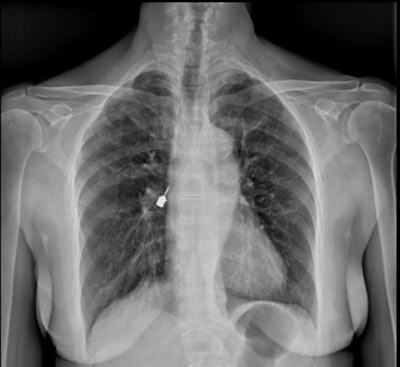

First, a chest x-ray was completed, which showed a 2-cm metallic foreign body within the patient's right airway. The object was consistent with a dental drill head that had been aspirated, the authors wrote.

Figure 1: Posteroanterior chest x-ray. A metallic foreign body (the drill head) is visible near the right hilum, supposedly located in the right airways. Images and captions courtesy of De Chiara et al. Licensed under CC BY-NC-ND 4.0.